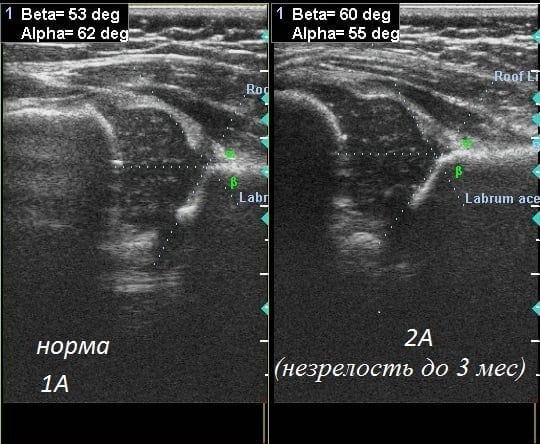

Допускается незначительное отклонение параметров углов примерно на 1-2°. Это может указывать, как на индивидуальные особенности строения таза, так и на развивающуюся дисплазию. В таких случаях терапия не проводится, а ребенок находится под контролем врачей. Ему назначается сонография примерно в 5 и 10 месяцев, считающихся возрастными точками. Степень дисплазии определяется по параметрам альфа- и бета-углов:

- альфа — углы, образуемые при скрещивании линий, проведенных от срединной стенки подвздошных костей, и линий, проводимых от нижних частей подвздошных костей к верхним краям вертлужных впадин;

- бета — угол, образованный верхними краями вертлужных впадин и центрами хрящевых пластинок.

Полученные после измерения углов параметры и становятся оценочным критерием нормального или патологического строения сочленения. Ниже представлена расшифровка значений углов, полученных при проведении УЗИ тазобедренного сустава у грудничка:

- нормальные параметры — угол альфа больше 60°, угол бета больше 55°,

- состояние предвывиха — значения угла альфа — 43-49°, угла бета — 70-77°;

- подвывих — угол альфа — меньше 43°, угол бета — больше 70°;

- вывих — угол альфа — меньше 43°, угол бета — больше 70°, при этом костная поверхность сильно вогнута, а хрящевой выступ деформирован.